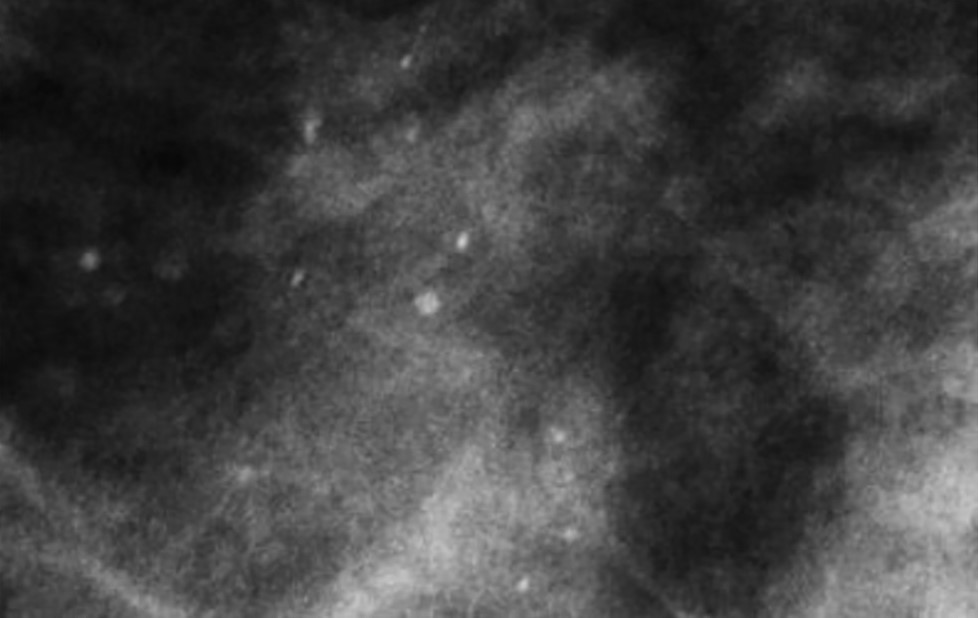

Множественные рассеянные точечные микрокальцинаты характерны для склерозирующего аденоза – доброкачественного состояния, при котором отмечается увеличение долек молочных желез и их дисторция окружающей фиброзной тканью [13] (Рис.7).